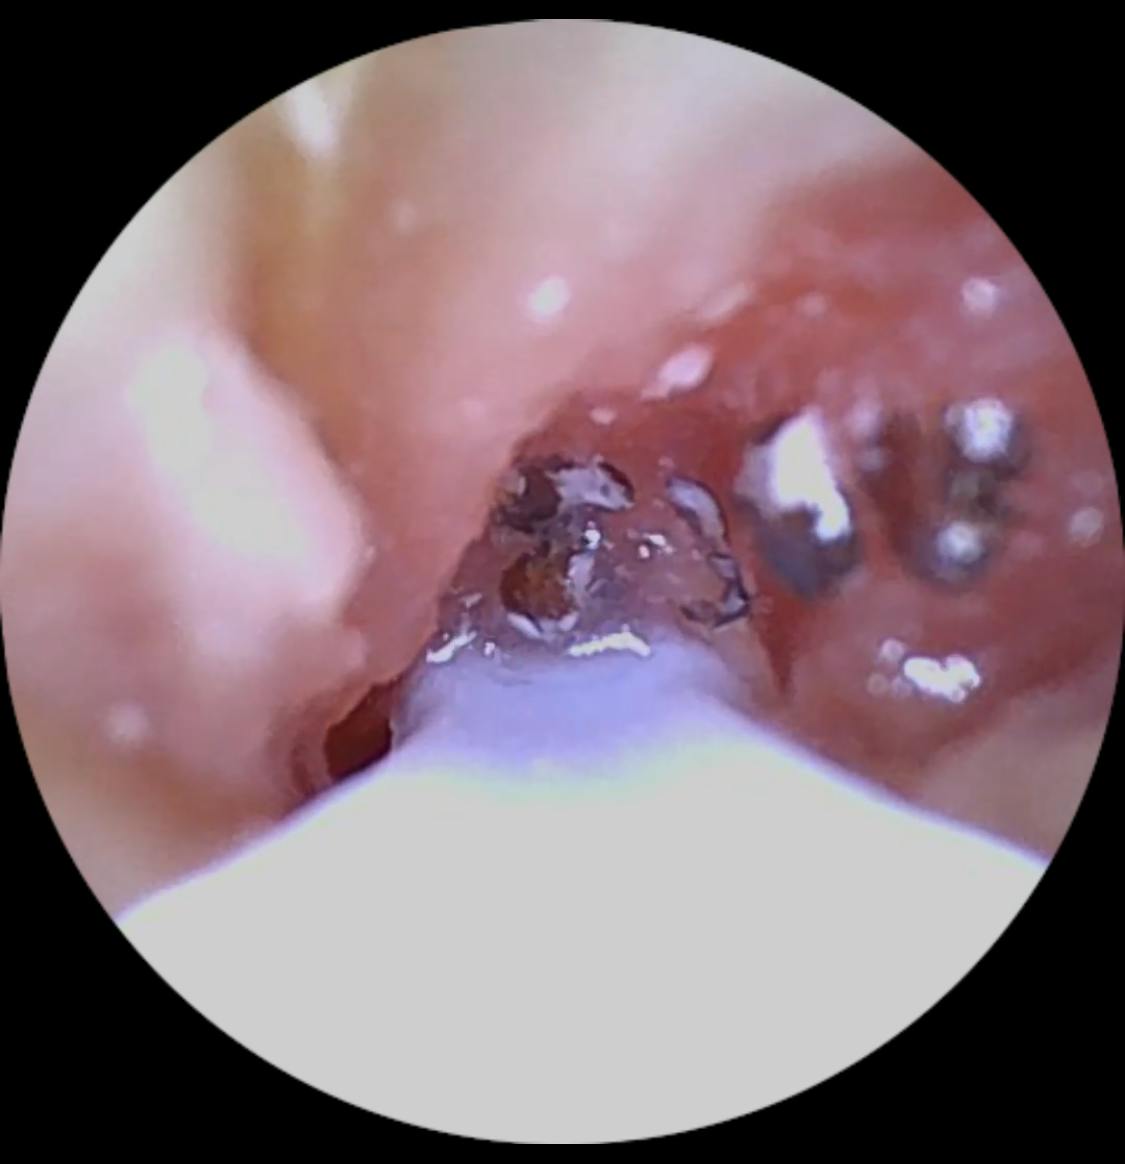

Ich bin wirklich überraschend begeistert von diesem Ohrenendoskop. Die Handhabung ist kinderleicht, die Verbindung zum Smartphone hat auf Anhieb funktioniert und die Bildqualität ist überraschend gut – gestochen scharf und detailreich. So konnte ich mir das Ohrinneres problemlos anschauen und erkennen, was los ist.

Besonders praktisch finde ich das schlanke Design und die integrierte Beleuchtung – dadurch sieht man selbst kleine Details sehr klar. Auch die mitgelieferten Aufsätze und Werkzeuge sind gut verarbeitet und machen die Anwendung noch einfacher und hygienischer.

Mit diesel Gerät kann ich selbst in regelmäßigen Abständen das Ohr vom gröbsten Ohrenschmalz befreien. Mit diesem Gerät tut es überhaupt nicht weh, die Aufnahmen der Kamera sind sehr gut. Mit etwas Geduld, Übung und Vorsicht kann man das Ohr wirklich sehr gut reinigen, ohne es zu verletzen. Ich kann das Produkt ohne Vorbehalte weiterempfehlen und würde es wieder kaufen.

Meine Ohren waren ziemlich dreckig, hab damit aber fast alles rausbekommen. Bin zufrieden

Meine Ohren waren soooo verstopft, das hätte ich mir nie gedacht. Hab aber zum Glück alles rausbekommen, das Gefühl ist auch richtig angenehm gewesen, fast schon satisfying

Hier findest du echte Kundenmeinungen über den Miluna™ Pro – den beliebten visuellen Ohrenreiniger mit HD-Kamera, LED-Beleuchtung und sanften CleanScoop™-Aufsätzen. Bereits über 40.000 Kund:innen aus dem deutschsprachigen Raum haben unsere Ohrenreinigungslösung getestet und teilen auf dieser Seite ihre ehrlichen Erfahrungen – von der einfachen Anwendung bis zum Ergebnis nach der Reinigung.